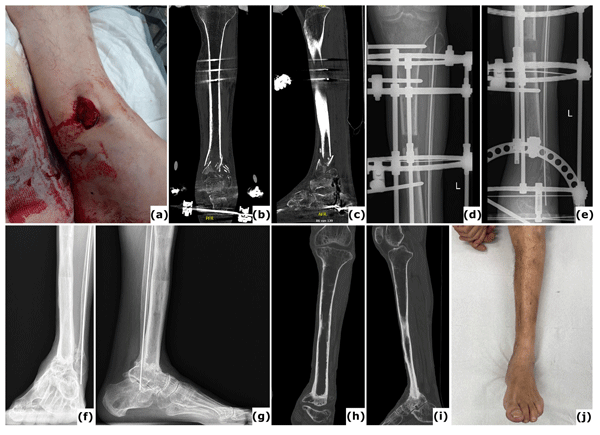

Complete talectomy for post-traumatic osteomyelitis (and/or avascular necrosis): report of a new technique

Daniel Pérez-Prieto, Alois Baumer, Jan Martinez-Lozano, Julian Aquilina, Paul Zamora, Albert Alier, and Lluïsa Sorlí

J. Bone Joint Infect., 10, 419–424, https://doi.org/10.5194/jbji-10-419-2025,https://doi.org/10.5194/jbji-10-419-2025, 2025

Short summary